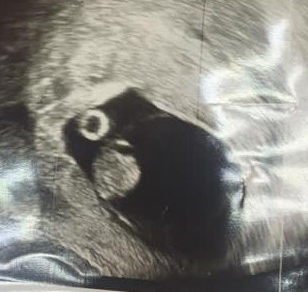

Для уточнения ситуации было проведено повторное УЗИ органов малого таза в динамике. Данные УЗИ от 20.07.2020: тело матки анатомически правильное, гематома на 15 мм выше плодного яйца. Толщина миометрия в зоне рубца 3 мм. Миоматозные узлы отсутствуют. В полости матки в области нижнего сегмента расположено одно плодное яйцо, 19 мм в диаметре (7–8 недель). В полости матки эмбрион: КТР 19 мм (соответствует восьми неделям беременности), хорион в области послеоперационного рубца. Сердцебиение эмбриона ритмичное, 173 удара в минуту. Шейка матки – внутренний зев сомкнут. Правый яичник не изменен, левый яичник содержит желтое тело диаметром 16 мм. Маточные трубы не визуализируются, свободной жидкости в сводах нет. Заключение: беременность 8–9 недель. Имплантация плодного яйца в области рубца на матке (рис. 1, 2).

Рис. 1. Трансвагинальное ультразвуковое исследование органов малого таза. Внутри плодного яйца определяются внезародышевые структуры – желточный мешок, хорион. Хорион в области послеоперационного рубца. Дата проведения: 20.07.2020